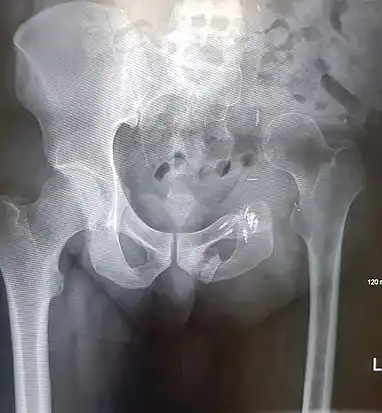

Prior to performing a hemipelvectomy, surgeons must possess detailed knowledge of the pelvic anatomy and its relation to the pelvic tumor.[1] Imaging studies such as conventional radiography, computed tomography, and magnetic resonance imaging help the surgeon visualize the anatomy and its relationship to the local pathology.[1] Surgical oncology techniques are utilized when resecting tumors of the pelvis.[1] Such techniques ensure that adequate resection margins are obtained at the time of surgery to minimize tumor recurrence.[1]

The Enneking and Dunham classification system was developed in 1978 to aid surgeons in characterizing pelvic resections.[1][3][4] This classification scheme breaks down pelvic resections into 3 subtypes: Type I, Type II, and Type III.[1][3][4] Type I resections involve removal of the ilium.[1][3][4] Type II resections involve removal of the peri-acetabular region.[1][3][4] Type III resections involve removal of the ischial and/or pubic region.[1][3]

Resection of pelvic bone typically requires subsequent reconstruction to ensure stability of the hip joint, particularly in internal hemipelvectomy.[1] Examples of pelvic reconstruction include the use of an allograft, autograft, or prosthesis to bridge the remaining ends of pelvic bone following resection.[1][4] Arthrodesis is a technique that can be used in internal hemipelvectomy to fix the proximal femur to a segment of pelvic bone for the purposes of stabilizing the lower extremity.[1][4]